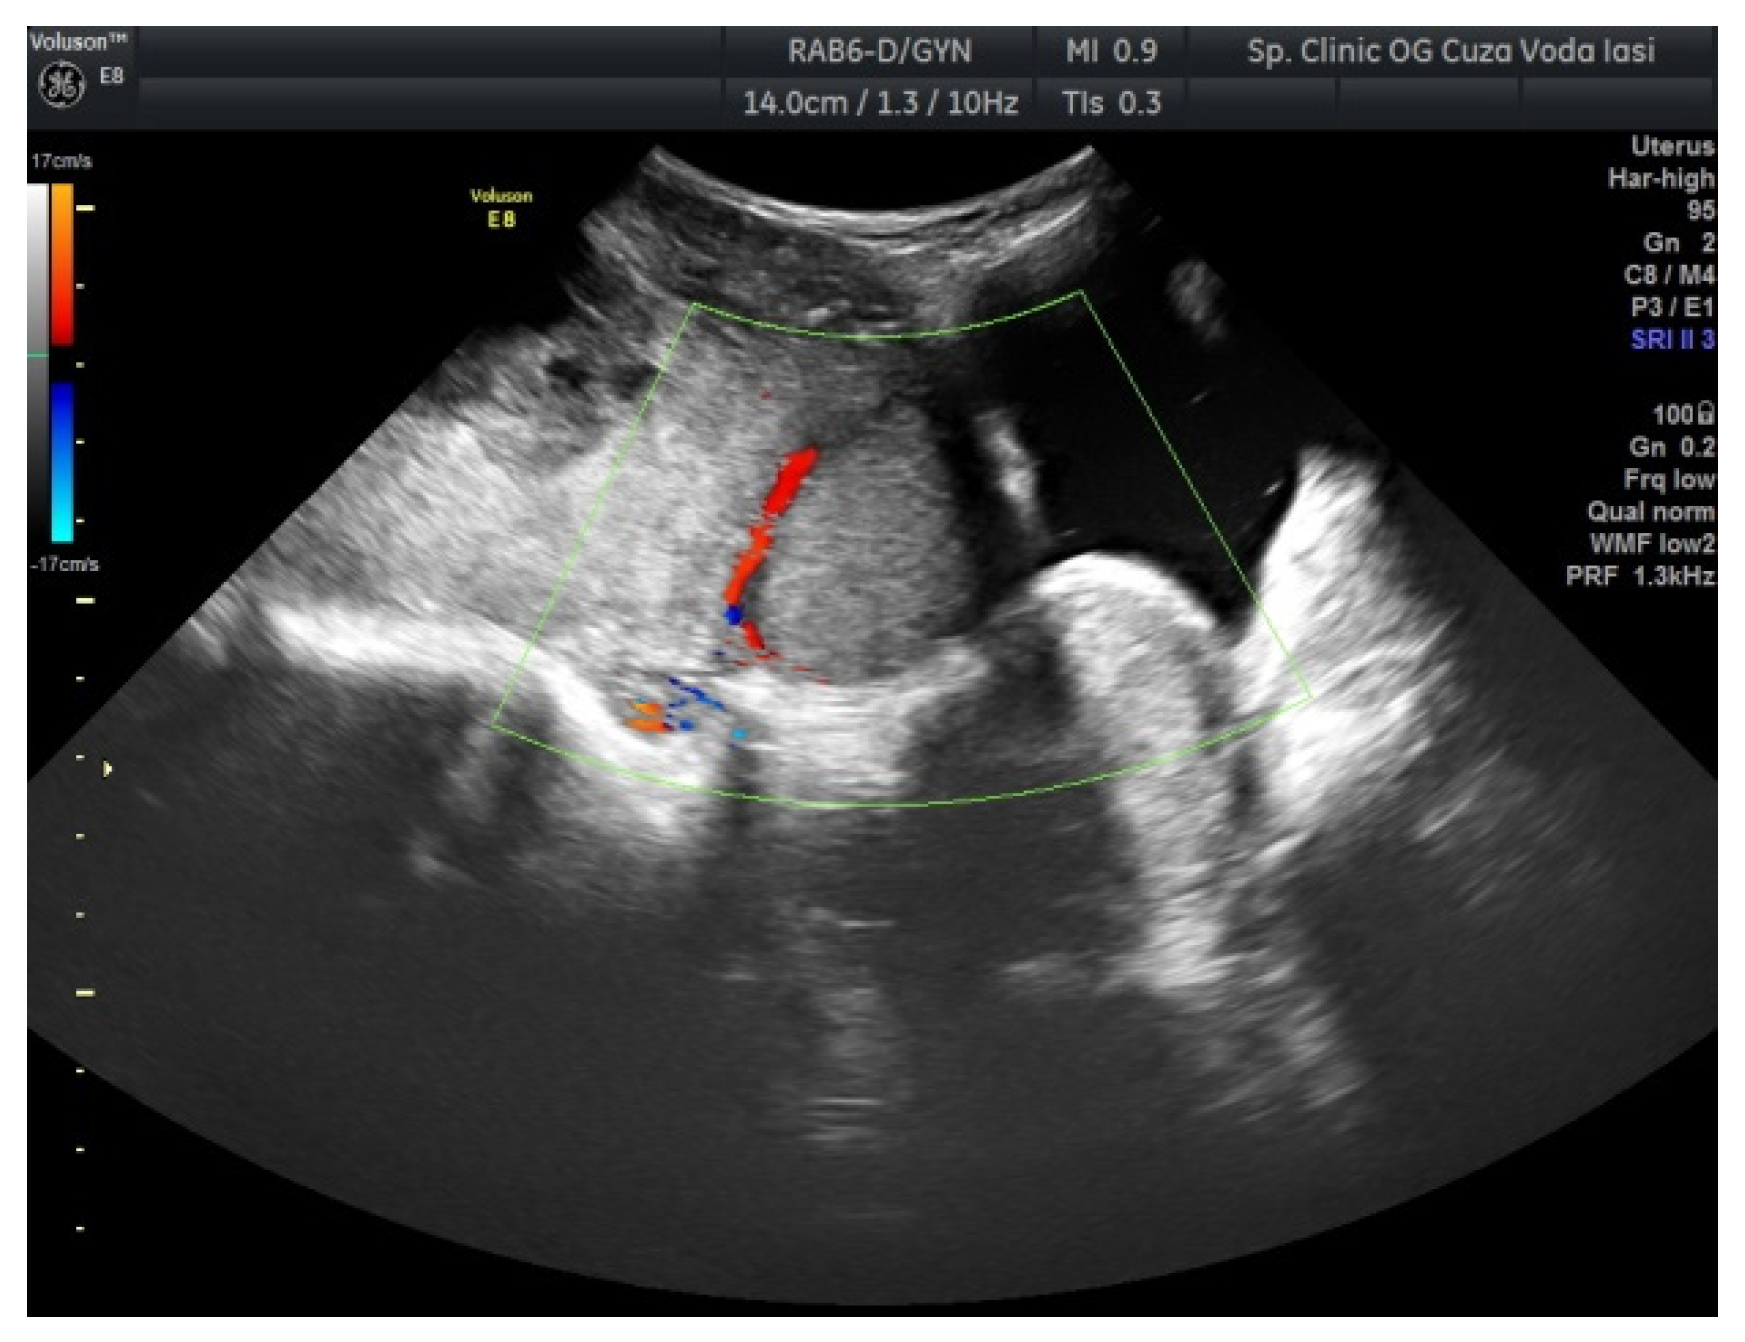

2. Case Presentation